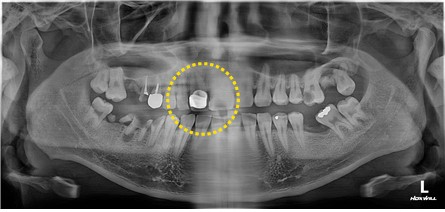

#12 예전에 cr치료를 한 부위인데 금이 간 상태로 인하여 내원해 주셨습니다.

cr치료를 한 치아는 #11임을 설명드리고 기존 변색된 레진 제거 후 #12 RF설명드리고 당일 치료해 드렸습니다.